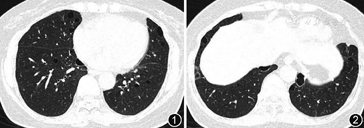

患者,60岁女性,因“间断气短1个月”至北京协和医院呼吸与危重症医学科门诊就诊。近1 个月来出现间断气短,无明显咳嗽、咯痰,无发热;近5年曾出现3次自发性气胸,既往无高血压、糖尿病等慢性病史。兄弟姐妹共4人,哥哥有气胸史。患者门诊胸部CT见双肺多发、大小不一的薄壁囊状透亮影(图1, 2),形状不规则(可见圆形、椭圆形和扁平状),部分融合,主要分布于中下肺及双肺基底部,邻近纵隔胸膜下。考虑伯特-霍格-杜布(Birt-Hogg-Dubé syndrome,BHD)综合征诊断可能性大,行外周血全外显子测序后确诊BHD综合征:染色体17p11.2区域存在约2 kb的拷贝数杂合缺失变异:主要累及FLCN 基因45号外显子及其相邻内含子。泌尿系超声:左肾小囊肿。BHD综合征是一种罕见常染色体显性遗传性疾病,特征为弥漫性肺部囊状病变、自发性气胸、皮肤纤维毛囊瘤或毛盘瘤和肾脏肿瘤;针对肺部囊性病变目前尚无有效的治疗药物,日常需要避免长途飞行、屏气负重等以减少自发性气胸的发生。本例患者有反复自发性气胸、双肺多发近胸膜分布为著的大小和形态不均一的囊泡影,结合基因检测后确诊BHD综合征。